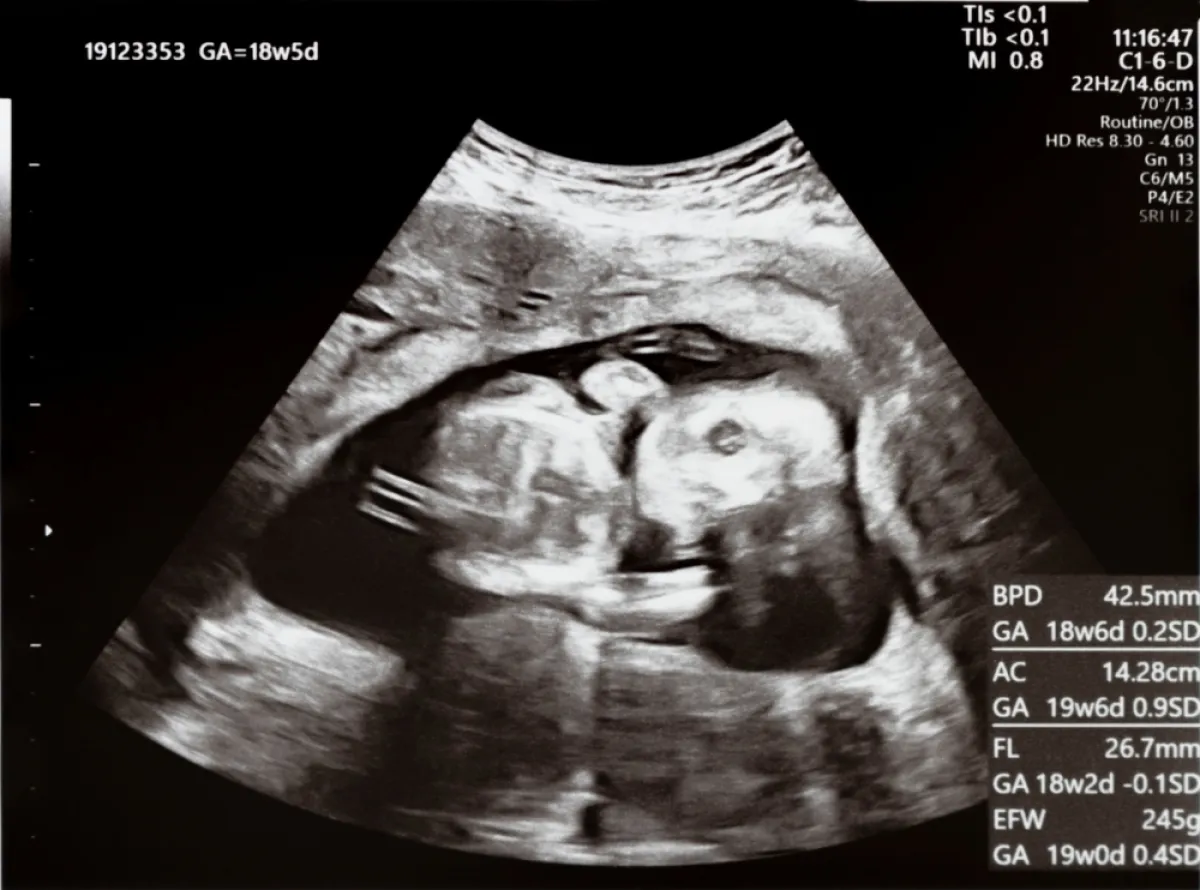

هذه المرحلة تسمى مرحلة النمو، وفيها يمكن سماع دقات القلب باستخدام سماعة الطبيب في حوالي الأسبوع العشرين، حيث يصبح الجنين قادراً على مص الإبهام ويبدأ الشعر في الظهور، وتفتح عين الجنين. في هذه المرحلة تشعر الأم بحركة تشبه الركلة، لكن، يمكن للجنين أن يعيش خارج الرحم. ولديه فرصة ضئيلة للبقاء على قيد الحياة، بالإضافة إلى ذلك، فإن نمو الرئتين لم يكتمل وهناك إمكانية التعرض للأمراض بشكل مرتفع بسبب عدم اكتمال عمل الجهاز المناعي.